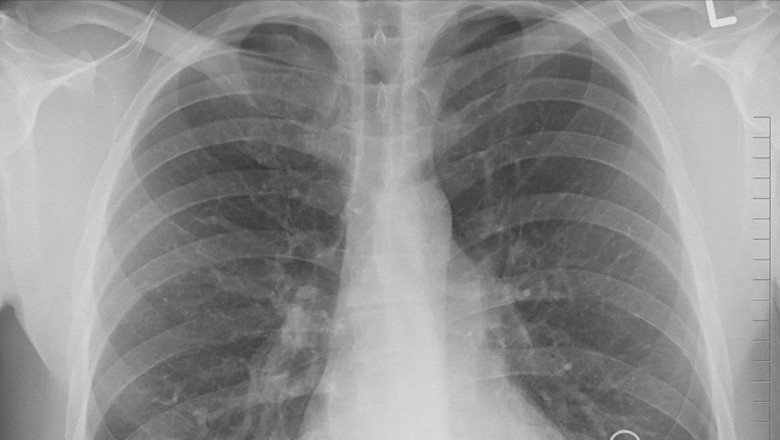

Türk Toraks Derneği Genel Başkanı Prof. Dr. İtil, TürkiyeTürk Toraks Derneği Genel Başkanı Prof. Dr. İtil, Türkiye'de yılda 35 bin kişinin akciğer kanseri tanısı aldığına dikkati çekerek "Ülkemiz, erkeklerde 100 bin kişide 41,7 oranı ile dünyada akciğer kanserinin en çok saptandığı ülkelerden biri" dedi